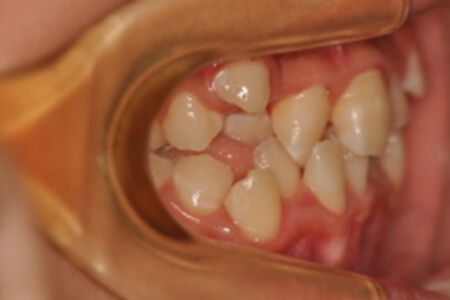

| 治療内容の詳細 | 初診時10歳の女性で、全体的ながたつきを主訴として来院されました。 検査の結果、交叉咬合を伴う、アングルⅠ級不正咬合と診断しました。 治療としては、反対咬合を改善するための装置で上顎前歯部を前方にだすと同時に上あごを広げ、セルフライゲーションブラケット装置(デーモンシステム)で歯の配列を行いました。 治療期間は2年11か月でした。 |